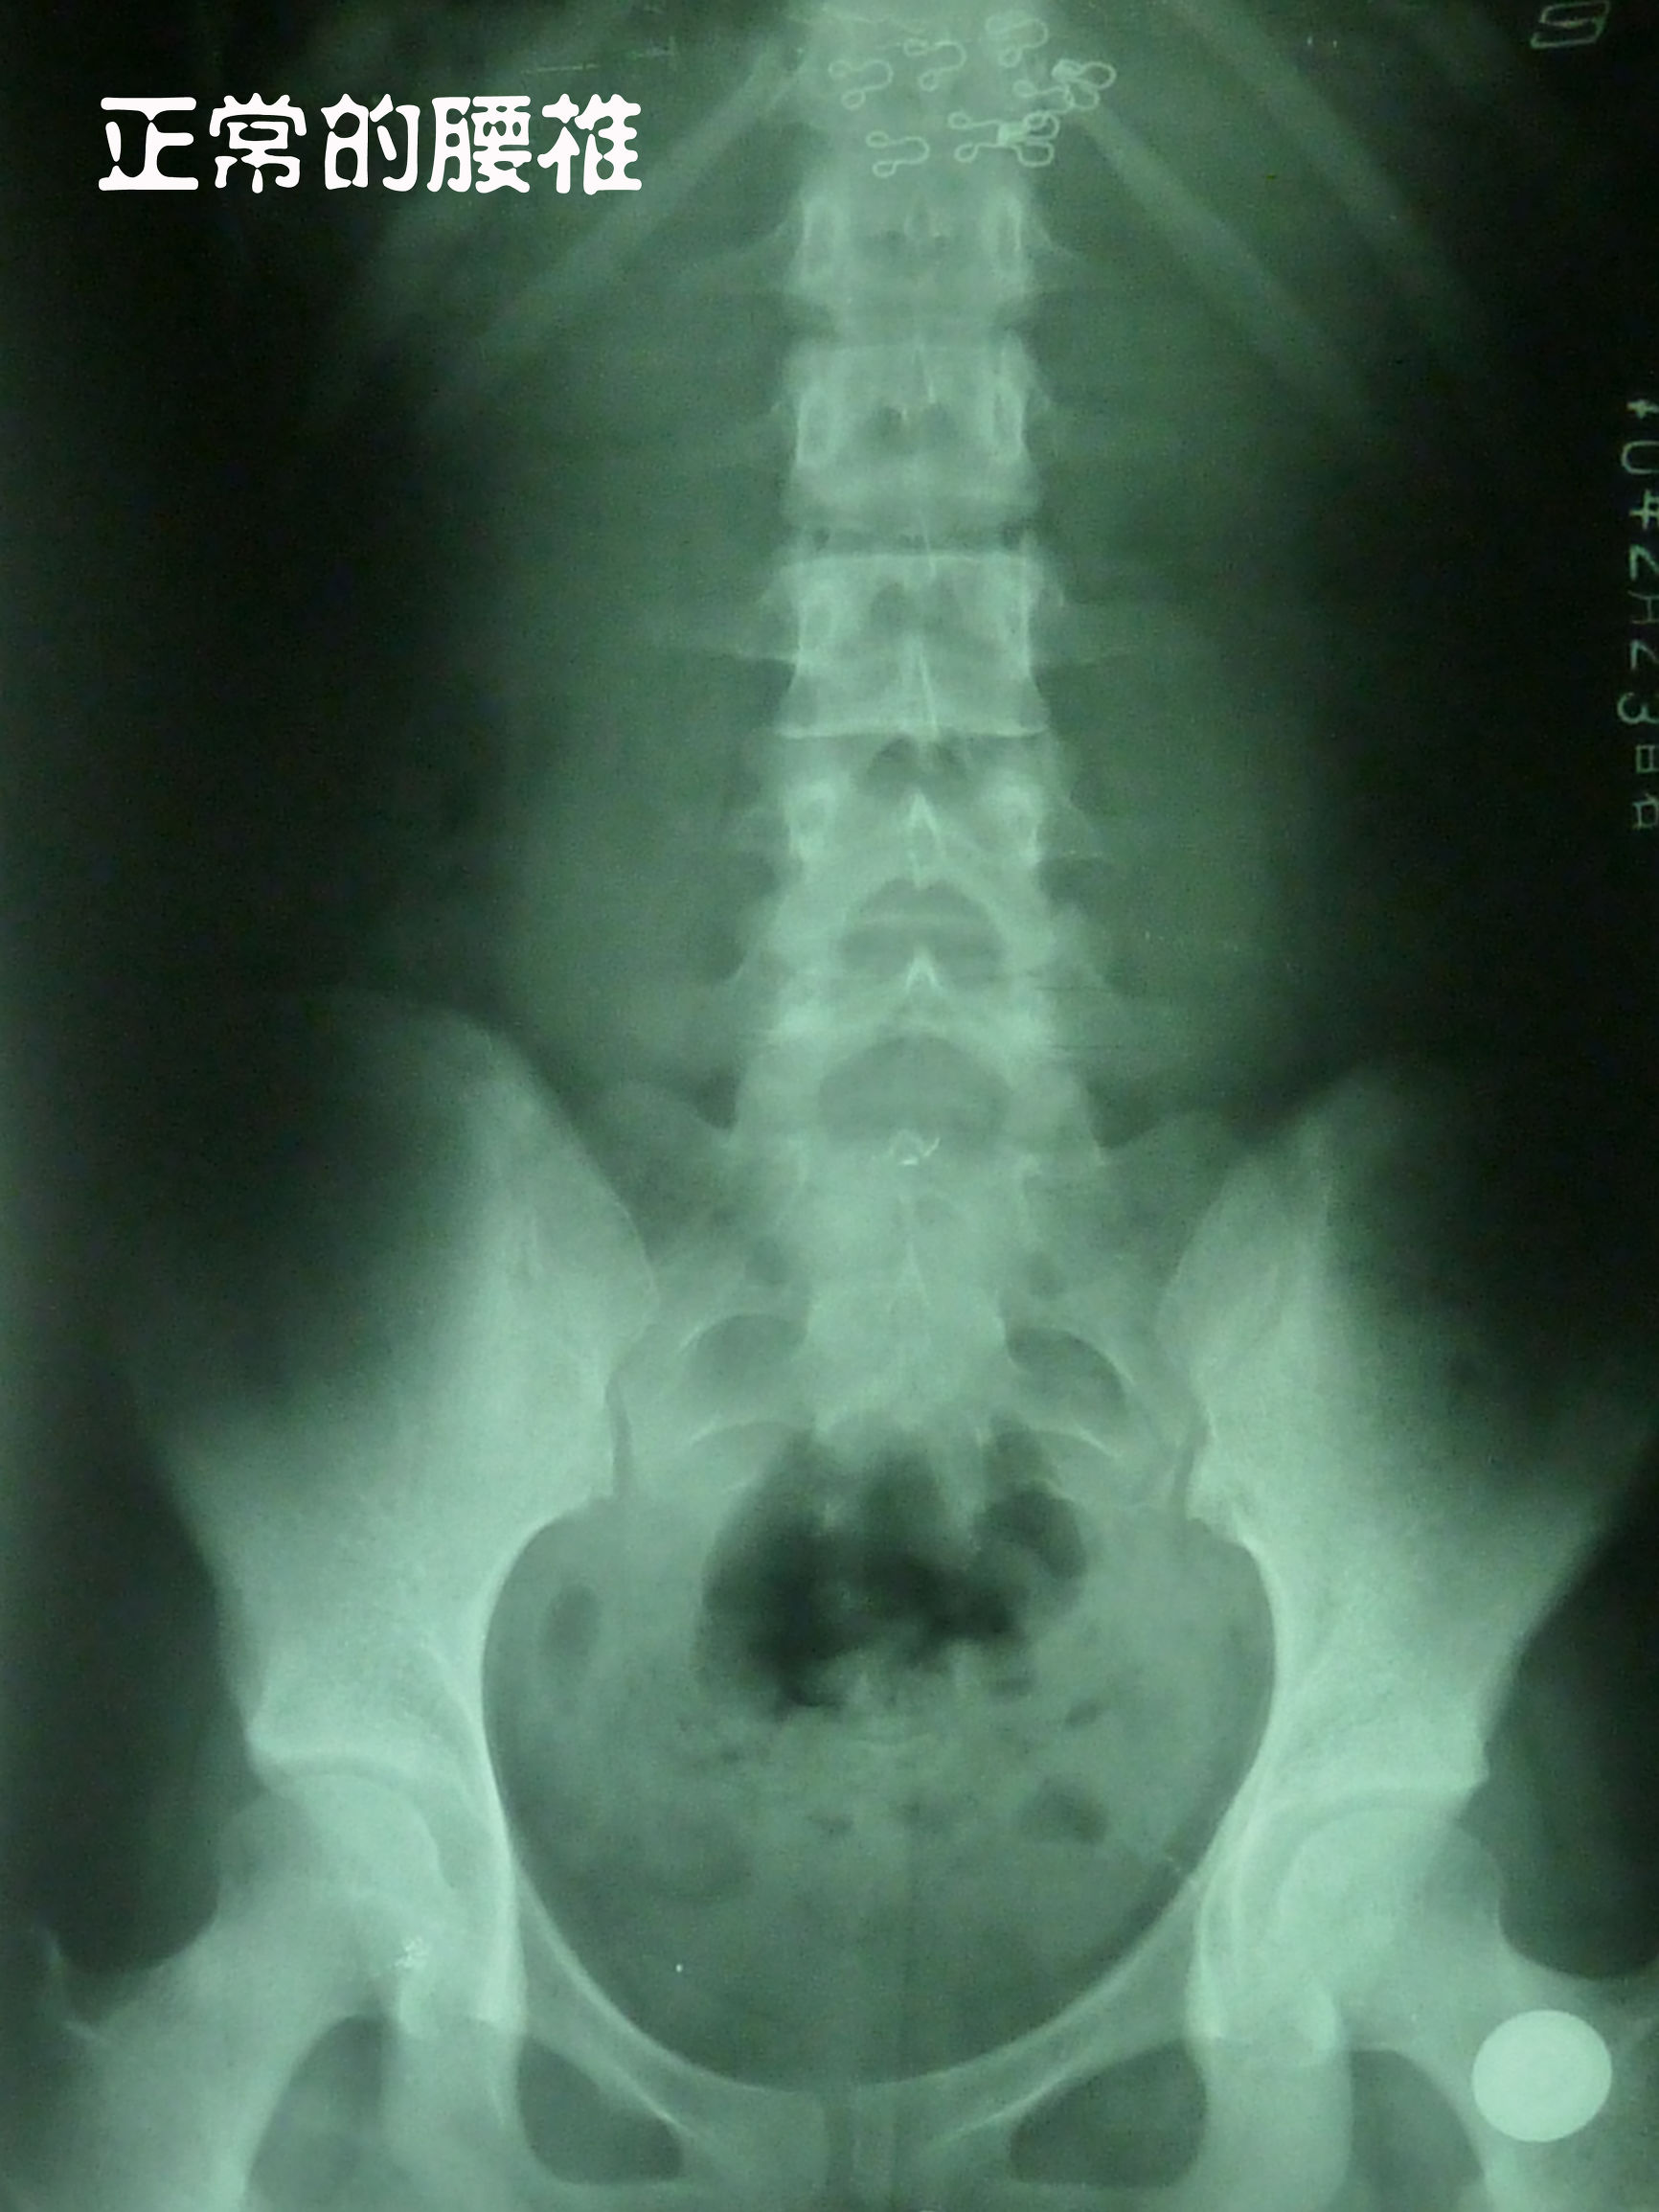

而腰椎结构好的人,一般就不容易得椎间盘突出,椎间盘受力均匀。

经临床研究发现,70%腰椎间盘突出的患者没有症状,说明这70%的患者根本没有压迫到神经,其中有一部分人仅表现为腰疼,而没有压迫神经腿麻的症状,但这并不是腰椎间盘突出所引起。引起腰疼的根本原因在于腰椎的变形和错位(比如有腰椎侧弯,椎体移位,腰椎反张,骨盆倾斜),从而导致脊柱生物力学失衡,腰椎受力不均匀,腰肌受牵拉而劳损 ,进而出现腰疼。而且 引起腰椎间盘突出的原因恰恰也是变形和错位。如果你的腰椎结构良好(曲度正常,没有侧弯,没有错位,没有骨盆倾斜),整个脊柱生物力学平衡,腰椎间盘受力均匀,就很难得腰椎间盘突出,除非受伤因素。